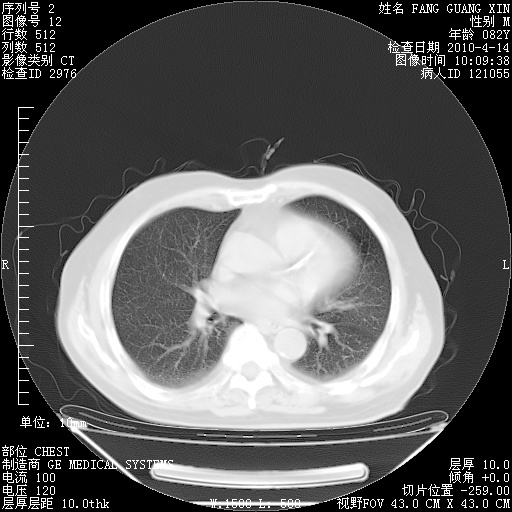

4月14日肺部CT

23.JPG

24.JPG

25.JPG

26.JPG

肺部CT平扫未见异常。